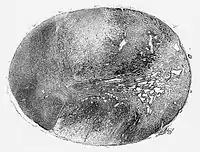

Macroscopic pathology of glioblastoma.